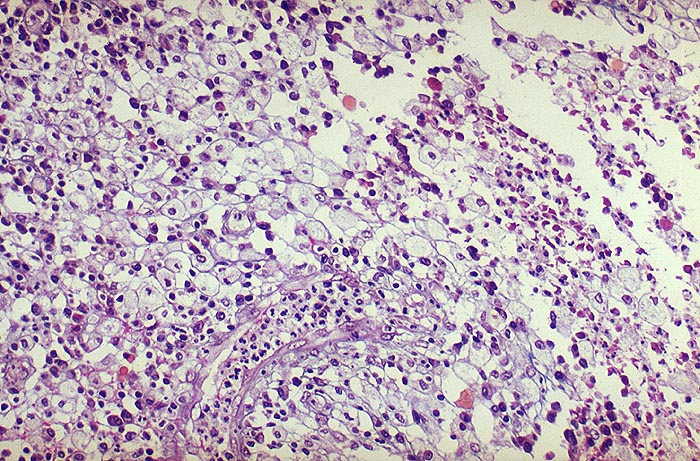

Xanthogranulomatöse Pyelonephritis

Typische Schaumzellen (Xanthomzellen) aus dem Granulationsgewebewall. Zwischen den Schaumzellen auch Lymphozyten-Plasmazellen sowie gelapptkernige Leukozyten.

Stets einseitige Pyelonephritis mit typischer Trias:

1. Obstruktion der ableitenden Harnwege zumeist durch Phosphatsteine

2. Coli oder Proteusinfekt

3. Störung der Leukozytenfunktion. Kommen tuberkuloide Granulome vor, wird fälschlicherweise oft eine Tuberkulose diagnostiziert. Bei Tuberkulose aber nie Schaumzellen. Die Malakoplakie der Niere ist im Gegensatz zur xanthogranulomatösen Pyelonephritis stets beidseitig.